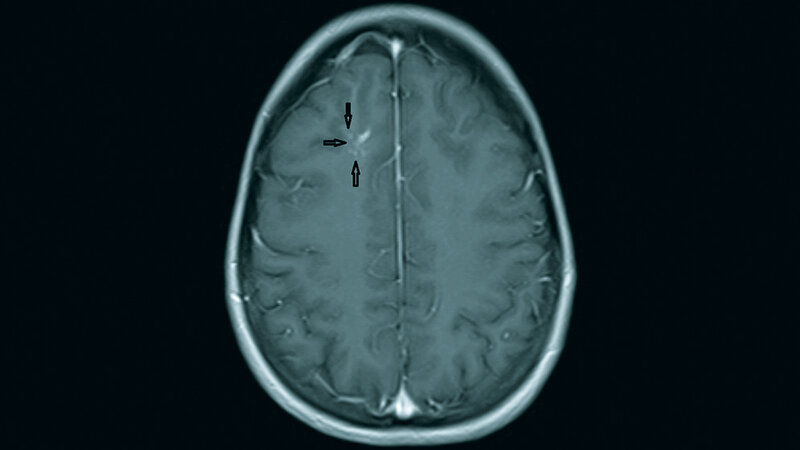

Zerebrale venöse Angiome stellen primär eine Variante der normalen venösen Gefäßarchitektur des Gehirns dar. Komplikationen können auftreten, und ihr Management erfordert ein Verständnis der Natur der Gefäßfehlbildung.

Developmental venous anomalies represent variations of the normal cerebral venous angioarchitecture. Complications can, however, occur and their management requires a thorough understanding of the nature of DVA.